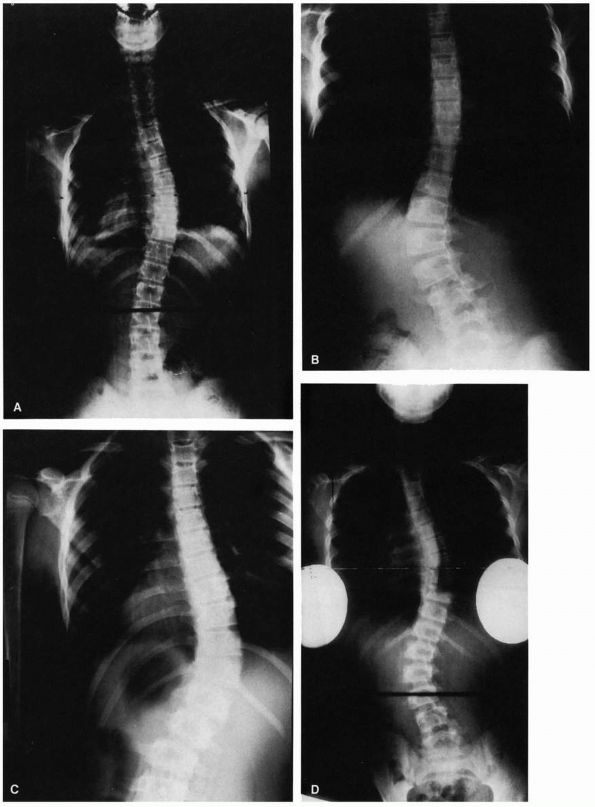

![]() |

FIGURE 16-10. (A)

Thoracic curve. Ninety percent right convexity involving an average of six vertebrae: apex—T8, T9; upper end vertebrae—T5, T6; lower end vertebrae—T11, T12. (B) Lumbar curve. Seventy percent left convexity involving an average of five vertebrae: apex—L1, L2; upper end vertebrae—T11, T12; lower end vertebrae—L3, L4. (C) Thoracolumbar curve. Eighty percent right convexity involving an average of six to eight vertebrae: apex—T11, T12; upper end vertebrae—T6, T7; lower end vertebrae—L1, L2. (D) Double curve. Ninety percent right thoracic convexity and left lumbar convexity. Thoracic component, average five vertebrae: apex—T7; upper end vertebrae—T5, T6; lower end vertebrae—T10. Lumbar component, average five vertebrae: apex—T2; upper end vertebra—T11; lower end vertebra—L4. |